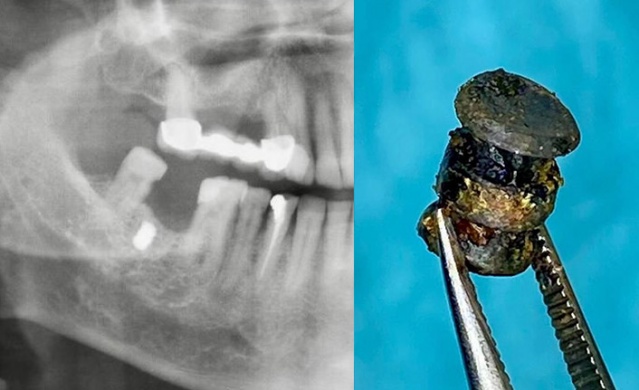

Akın'ı muayene ettikten sonra çekilen röntgen filmini inceleyen Dr. Öğretim Üyesi Yakup Gülnahar, yanağında bir parça olduğunu belirledi. Muayenede 15 yıl önce yaşadığı bir olayı hatırlayan Akın, benzinli hızar ile odun kestiği sırada zincirin koptuğunu ve daha sonra yanağında şişlik oluştuğunu söyledi.

Dr. Gülnahar'ın mıknatıs ile yaptığı kontrolde parçanın metal olduğu tespit edildi. Dr. Gülnahar, ameliyat ile Akın'ın yanağındaki metal zincir parçasını aldı.

Diş tedavisine gelince metal parçanın röntgen ile görüldüğünü belirten Faik Akın "Dr. Öğretim Üyesi Yakup Gülnahar, ağzımdaki şişliğin implant parçası olup, olmadığını sordu. Ben de kendisine implant yaptırmadığımı söyledim. Sonra aklıma 15 yıl önce yaşadığım hızar kazası geldi ve doktora anlattım. Yakup bey, mıknatıs ile kontrolü sonrası yanağımdaki parçanın metal olduğunu belirledi.

15 yıl önce benzinli hızar ile çalışırken zincir koparak çeneme çarpmıştı. Parça yanağıma girmiş ve bunu fark etmemişim. 15 yıl yanağımdaki bu şişlikle yaşadım. Başarılı bir operasyon ile aldılar. Şu anda hiçbir şeyim yok" dedi.

u200bDr. Öğretim Üyesi Yakup Gülnahar da "Faik bey, rutin diş tedavisi için bize geldi. İstenilen röntgen filminde bir cisme denk geldik. Kendisine 'İmplant yaptırdınız mı?' diye sordum. 'Hayır' dedi. Bu sefer, hasta geçmişinde yaşadığı bir kazadan bahsetti. Kontrol ettiğimiz de mıknatısın şişliği çektiğini gördük. Başarılı bir operasyon ile demir parçasını aldık. Hasta şu anda gayet iyi" diye konuştu.